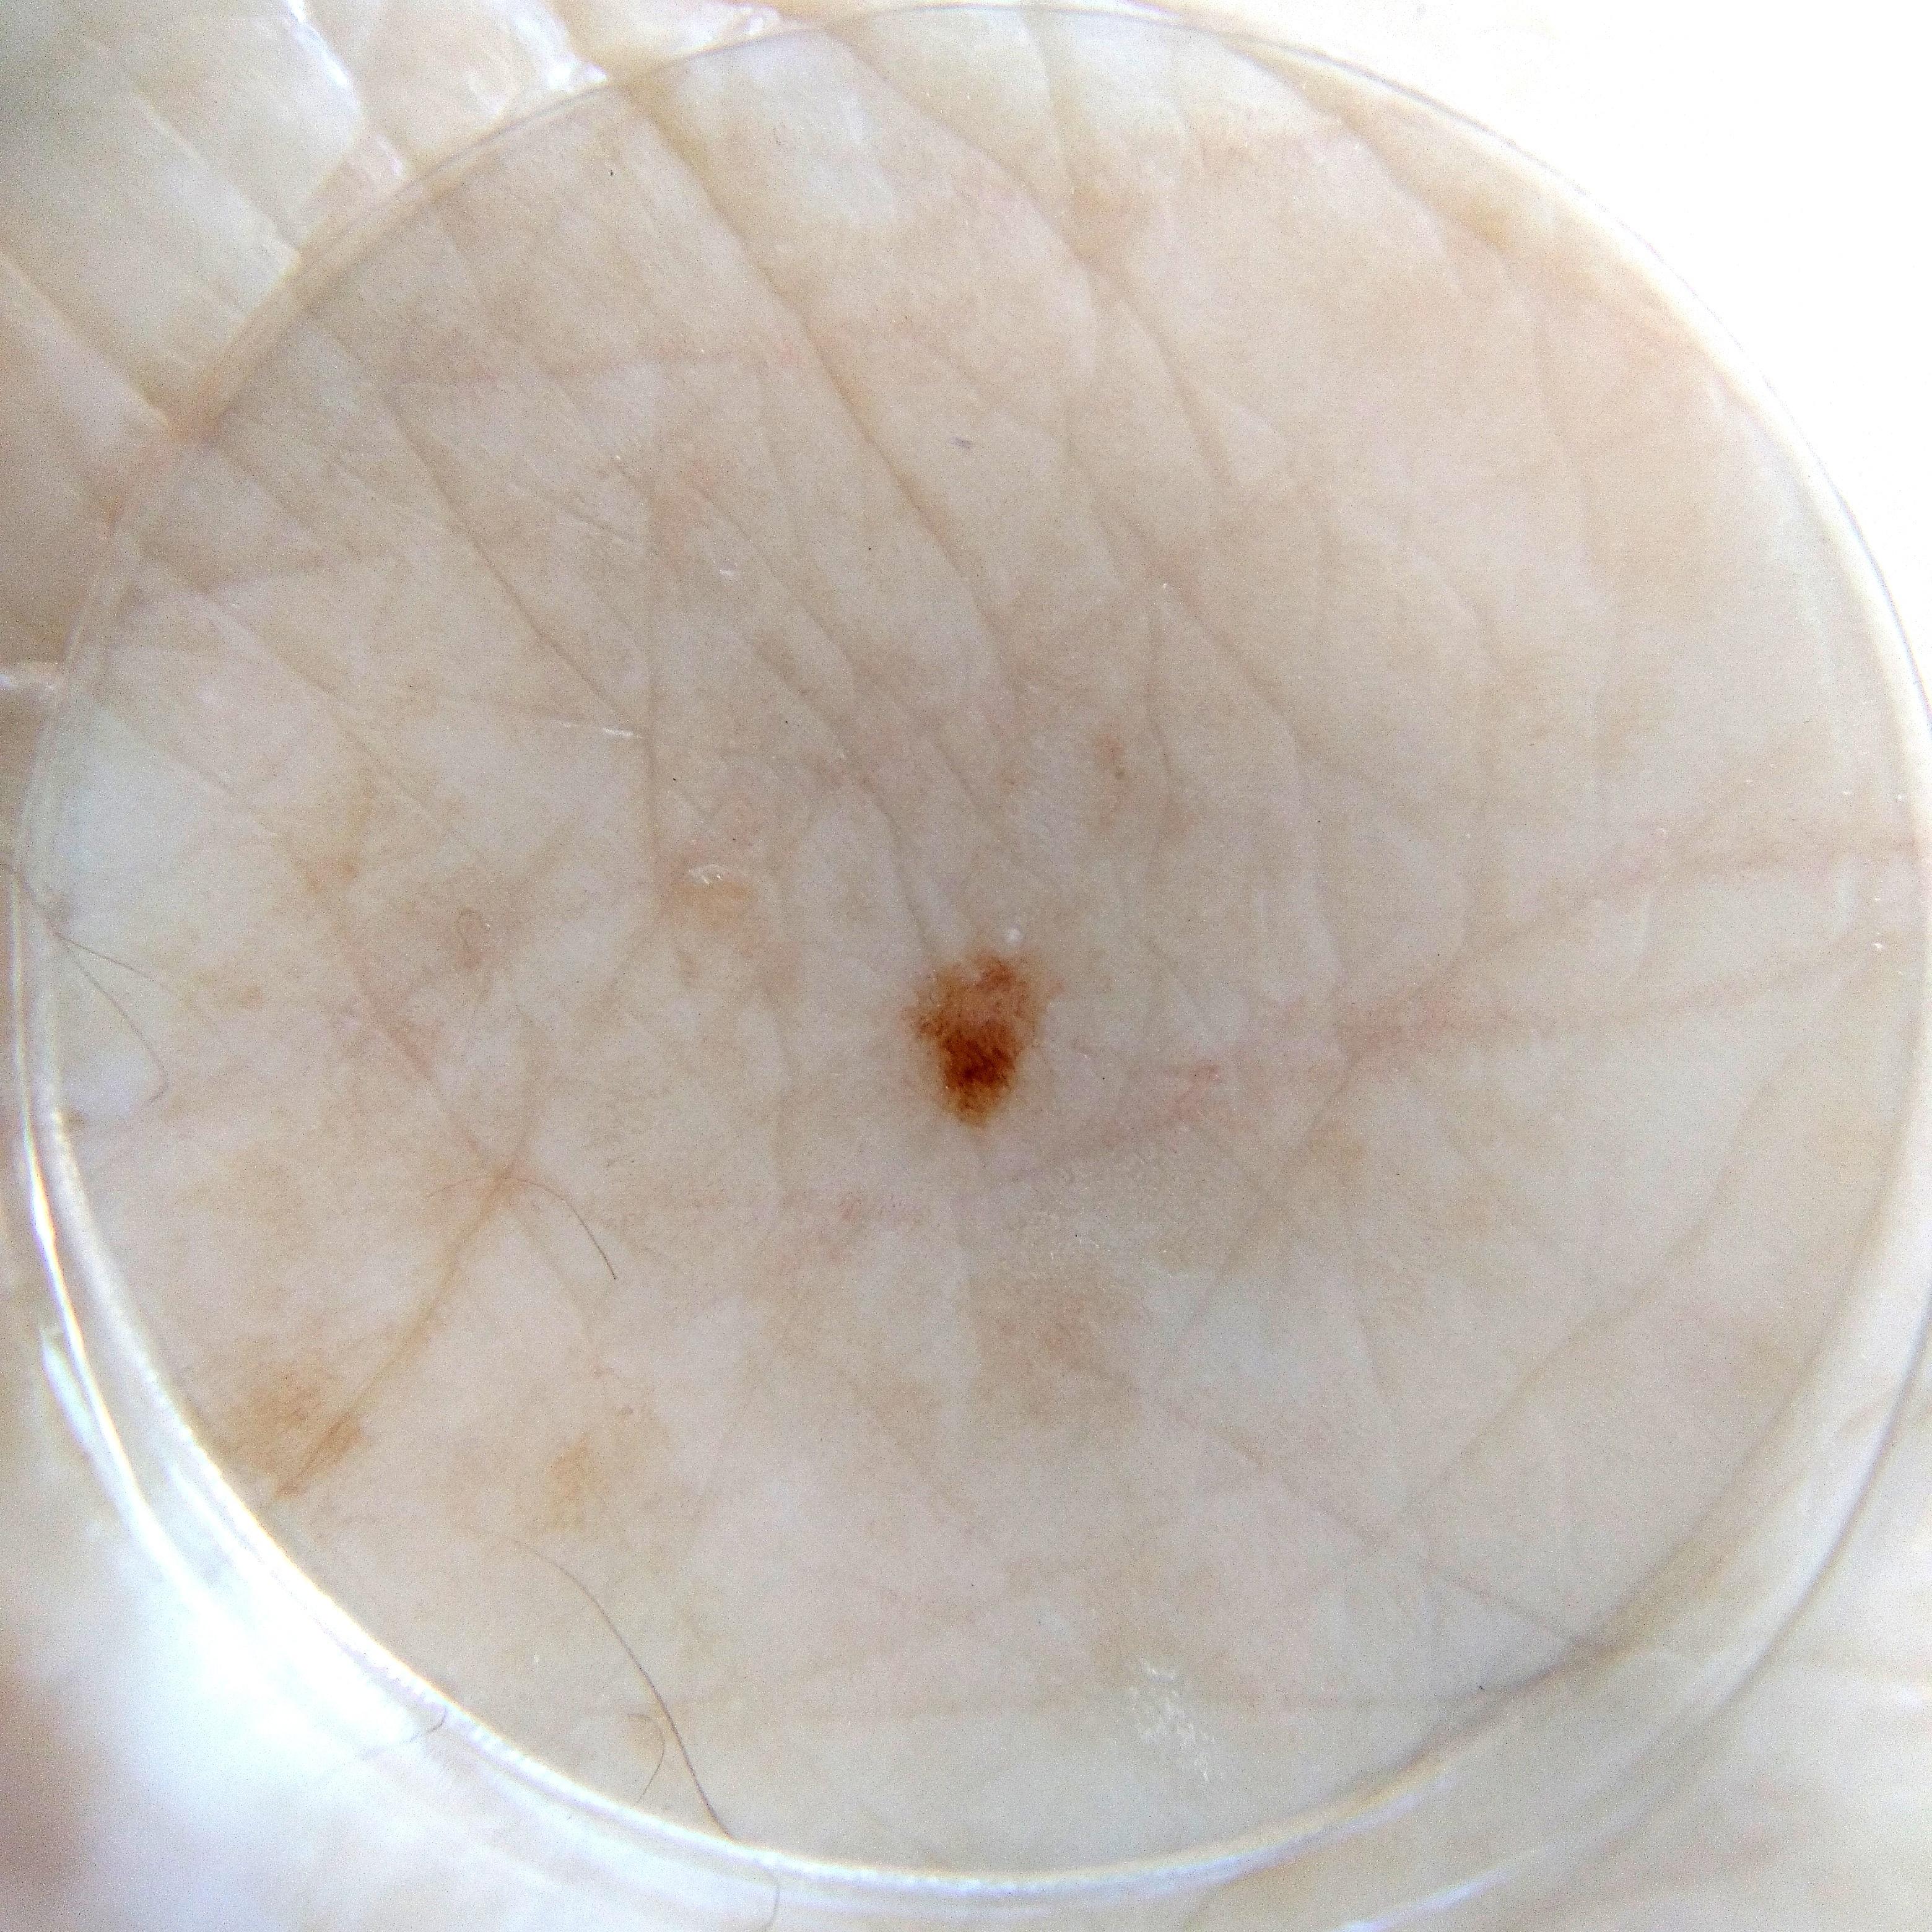

ISIC_7374896

1003 x 1003

acquisition_day 109

age_approx 75

anatom_site_1 Trunk

anatom_site_2 Posterior trunk

anatom_site_general posterior torso

concomitant_biopsy False

diagnosis_1 Benign

diagnosis_confirm_type single image expert consensus

family_hx_mm True

fitzpatrick_skin_type I

image_manipulation instrument only

image_type dermoscopic

lesion_id IL_3496589

patient_id IP_5171716

personal_hx_mm True

sex male